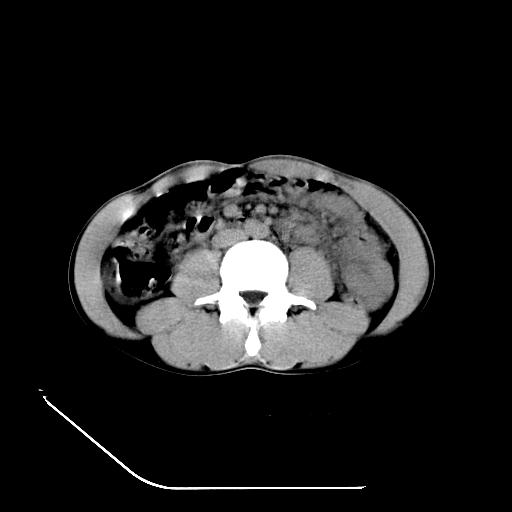

m-25y 高空堕落 12 月5号

12月7号病人尿量200ml/24h 急查双肾ct

左肾挫裂伤并肾周血肿;

左肾挫裂伤并肾周血肿

支持 : 左肾挫裂伤并肾周血肿

支持:1、左肾挫裂伤并肾周血肿;

2、少量腹水;

3、左肾旋转不良;

4、反射性肠淤张。

3、反射性肠淤张。